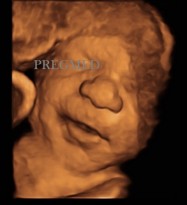

Fot. Obrazy twarzy płodu za pomocą techniki 3D/4D

Obraz twarzy płodu za pomocą techniki 3D 3D Mimika płodu w 3D